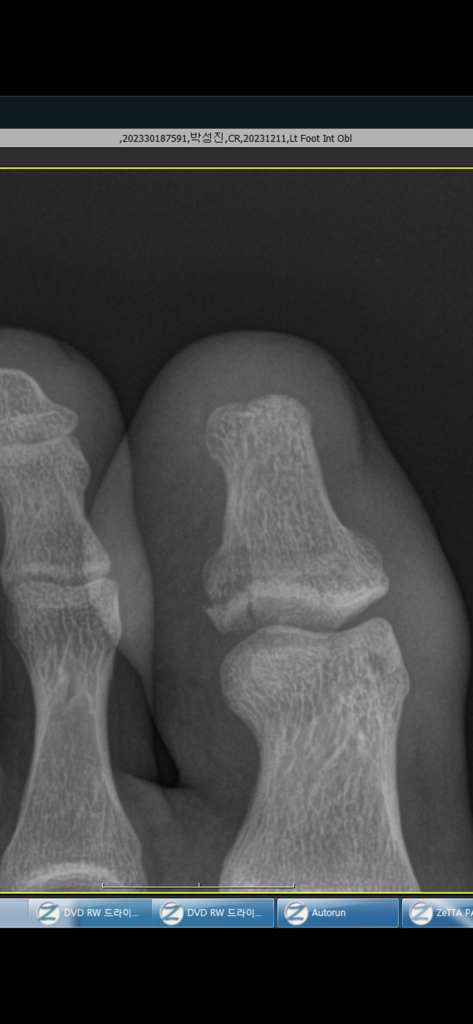

그리고 15일 후인 12월26일인 날에 가서 다시 엑스레이를 찍었 는데

이렇게 원위지골의 전위가 발생하여 불유합 가능성이 높다고 진 단을 받았습니다. 저렇게 뼈가 조각나서 전위가 발생했네요.

1) 혹시 수술적 치료를 하면 핀을 박는 수술을 하나요? 아니면 저 조각난 뼈를 제거하는 수술을 하나요?

2) 저정도 크기의 뼈조각이면 핀으로 고정할 수 있는 정도인가 요?

고정하기엔 크기가 너무 작아서 제거하는걸 고려해볼수 있을것 같습니다.